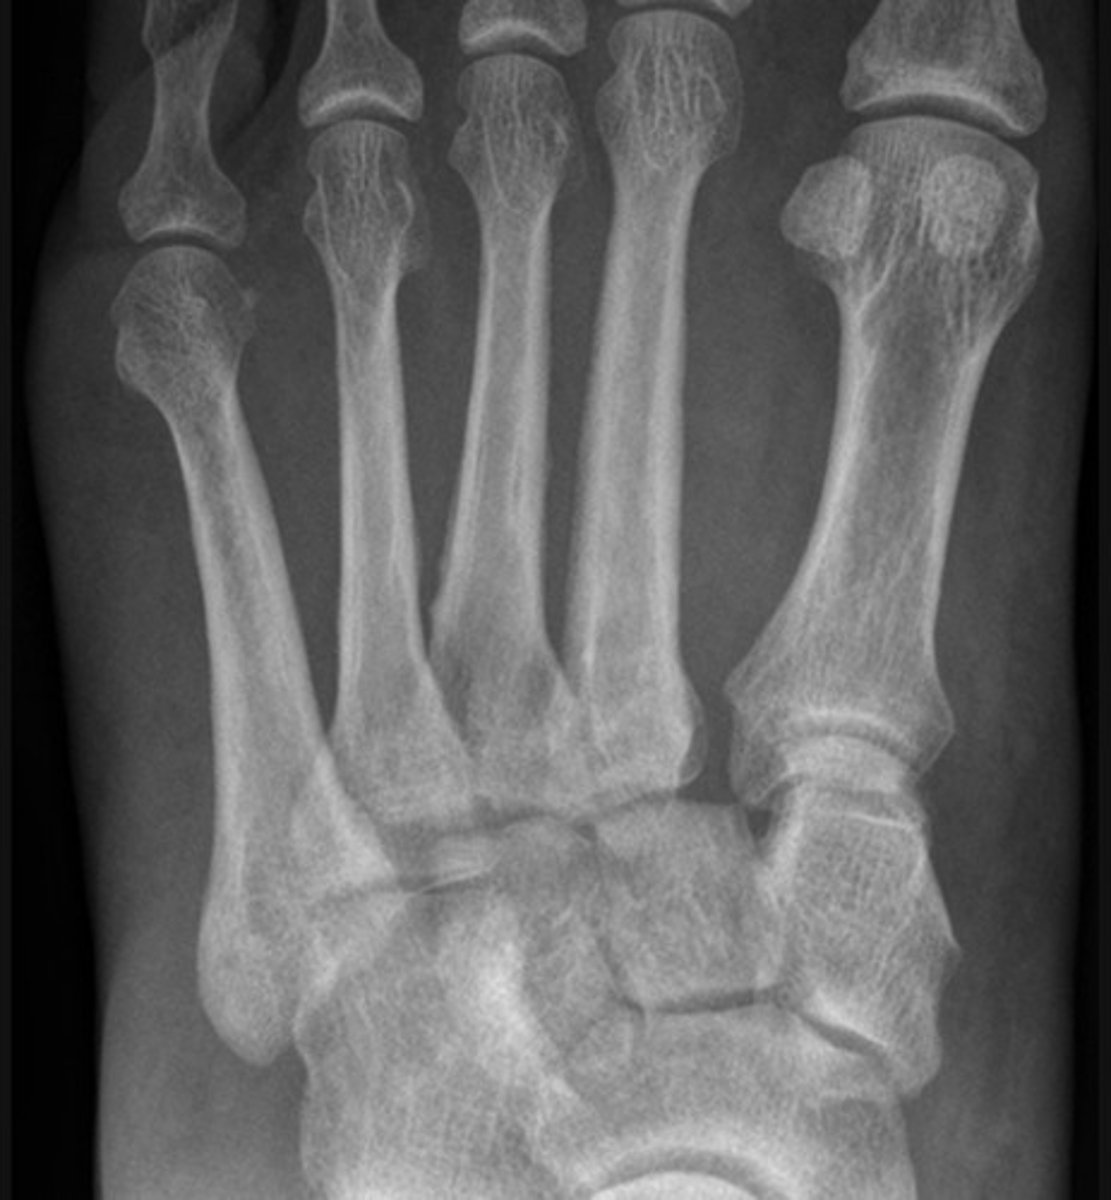

Lisfranc injury

base of 5th metatarsal fracture

dislocation of the proximal phalanx of the big toe at the MTPJ (metatarsophalangeal joint)